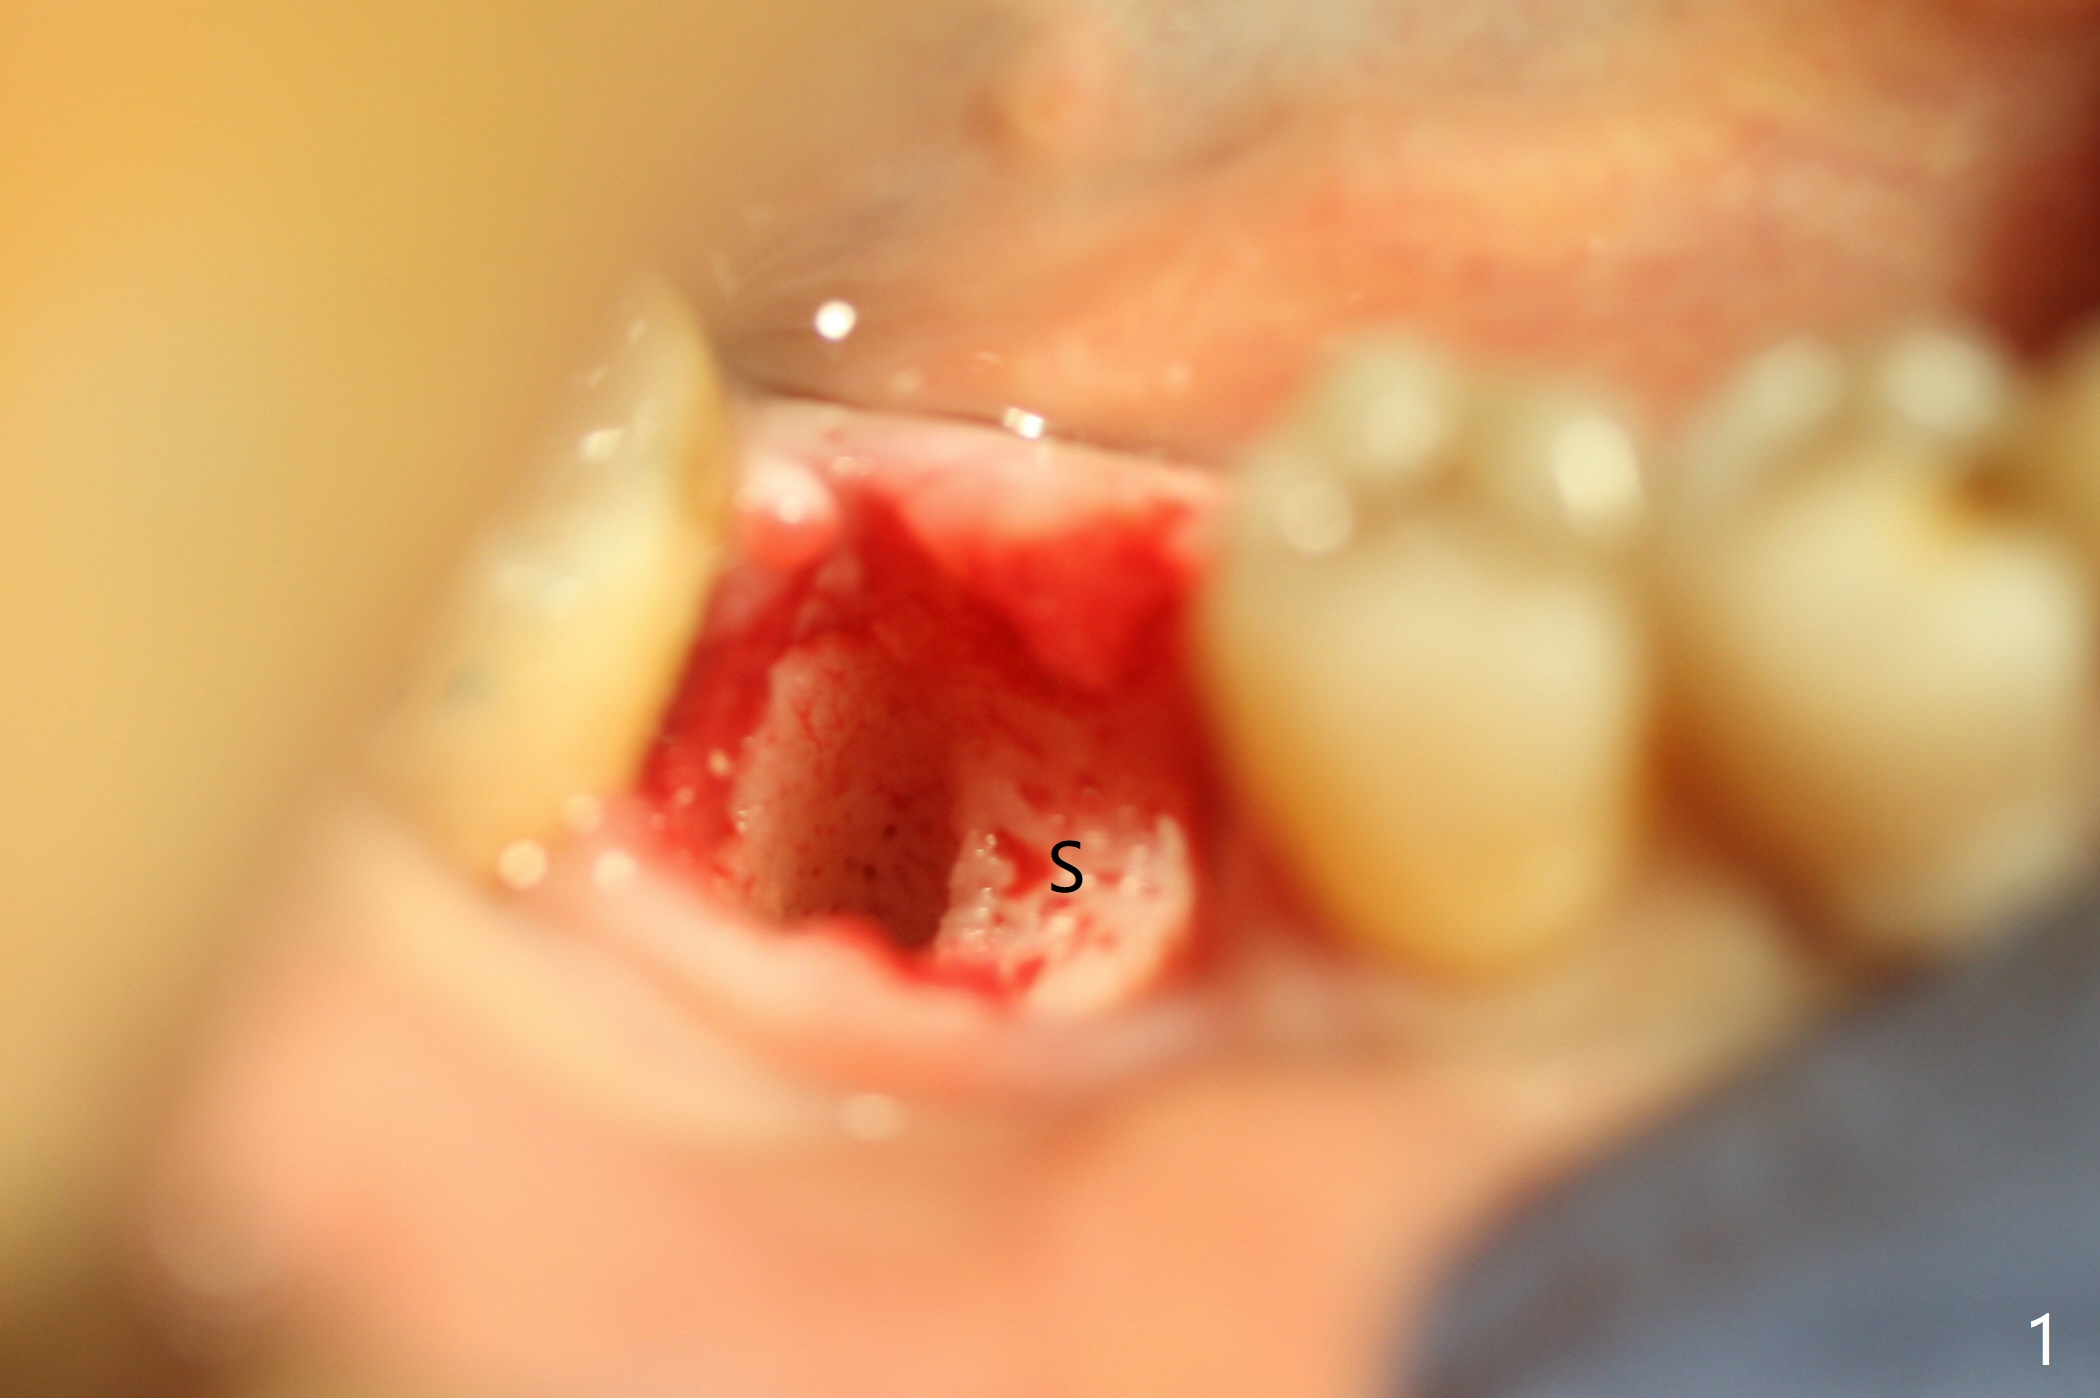

After extraction of #30 (Fig.1 (S: septum)), a 5x11.5 mm implant is placed with guide mainly in the mesial socket (mesial to the septum (S) with >35 Ncm; after immediate placement of a 6.5x4(3) mm abutment, allograft is placed (Fig.2 *). An immediate provisional is fabricated to hold the bone graft in place (Fig.3 P). To prevent micro-movement, the provisional has clearance from the opposing dentition (Fig.4 *, nonfunctional). There is not too much loss of bone graft 4 months postop (Fig.5). In fact the mesial and distal sockets heal. The implant plateau is covered with the bone 8 months post cementation (Fig.6 arrowheads ( *: addition of porcelain for the distal gingival embrasure)).